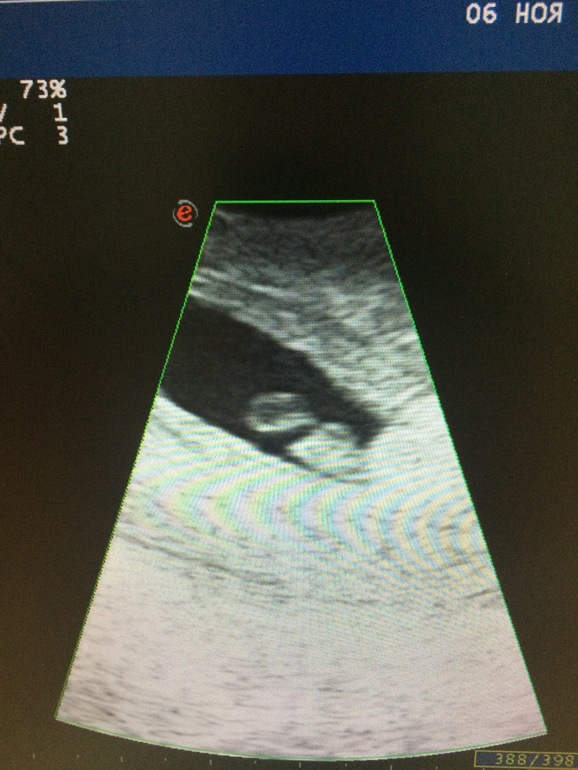

была только что у врача и на узи, сказал что все хорошо с плодом, плод вырос и яйцо тоже, приписал Элевит и йодомарин, сказал конечно что незаниматися ПА пока. все равно переживаючто значили те выделения рано после ПА, желто кориснев которых было много до обеда.фото узи :)